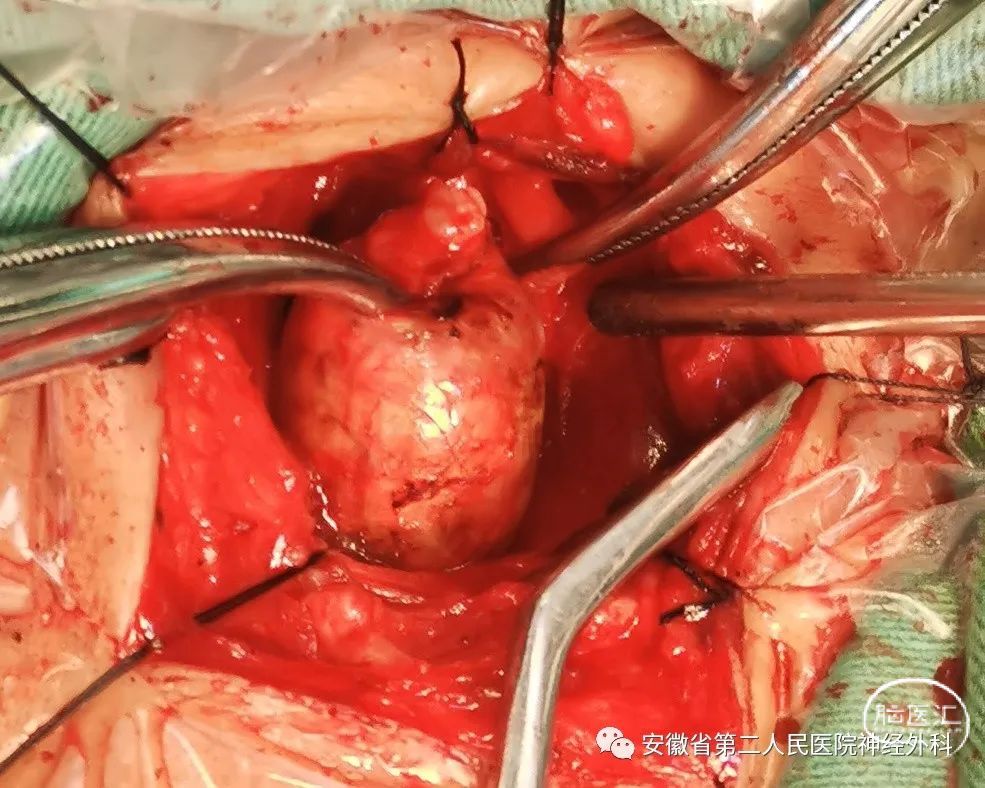

神经电生理监测下颈前外侧椎间孔入路

切除肿瘤主体

以上两个病例充分展示了安徽省第二人民医院神经外科在脊柱脊髓疾病诊疗技术上的硬实力,并已处于国内先进水平行列,特别是第二例“哑铃型”椎管内外肿瘤,手术难度非常高。目前我科常规开展多项诊疗项目和前沿新技术:1.颅脑创伤个体化精准救治技术,2.脑出血的综合、精准化治理技术,3.神经肿瘤的综合治疗技术(颅内及脊髓),4.脑血管病的综合治疗技术,5.功能性疾病治疗新技术。现我科可以处理的脊柱脊髓疾病有:脊柱脊髓肿瘤,骶管囊肿,脊椎椎间盘突出,脊髓血管畸形,小脑扁桃体下疝畸形,脊髓栓系综合征等。